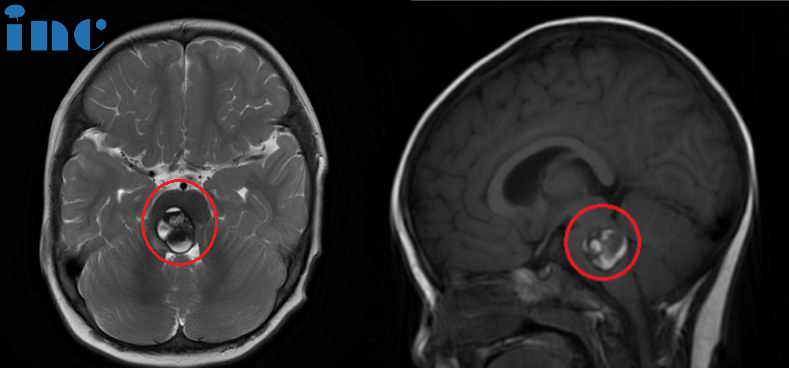

聪聪的脑干海绵状血管瘤病变位置

术前:脑桥占位性病变。临床表现包括双眼斜视、畏光、面瘫、频发不自主扭头动作及行走稍有不稳。头颅磁共振成像(红色区域)显示:脑桥血肿,可见16 x 22 x 21mm肿块,第四脑室受压变窄。